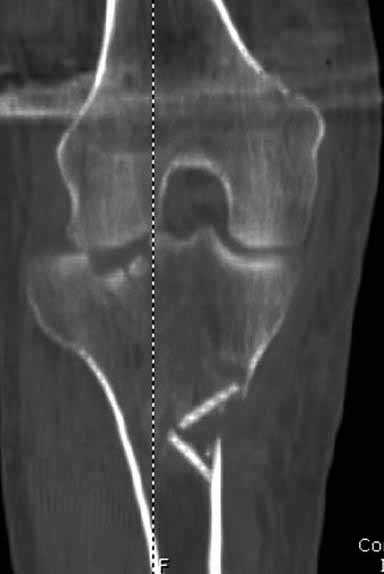

На снимке типичный перелом медиального тибиал плато с передним смещением (подвывих) по Schatzker IV. Консервативное лечение без медиальной опоры не может удержать деформирующие силы, и из-за вторичного смещения мыщелка конечность смещается в варус. Кроме передних смещений еще встречаются сложные фронтальные варианты переломов, и тогда голень подвывихивается кпереди.

А в данном случае мыщелок сросся со смещением кпереди и ротирован. За счет интактной наружной колонны опороспособность конечности сохранена, но остается варус и экстензия конечности. Для предоперационного расчета необходимо сделать на всю длину конечности рентгенограмму, а в остром периоде КТ и 3-мерный снимок помогут лучше ориентироваться в характере перелома.

Остеотомия с разворотом медиального мыщелка, и для фиксации можно применить параллельные субхондральные межмыщелковые шурупы. Дополнительная медиальная Smith-Nephew PERI-LOC™ (Periarticular Locked Plating System) пластина. При отсутствии специальной пластины можно адаптировать Tomofix для высокой остеотомии. Доступ прямой медиальный через pes anserinus или через интервал pes с medial gastrocnemeus.